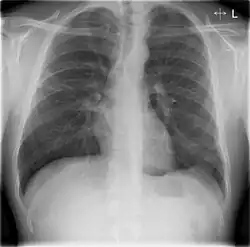

Chest X-rays and X-ray computed tomography (CT) can reveal areas of opacity (seen as white), indicating consolidation.[14] CAP does not always appear on x-rays, sometimes because the disease is in its initial stages or involves a part of the lung not clearly visible on x-ray. In some cases, chest CT can reveal pneumonia not seen on x-rays. However, congestive heart failure or other types of lung damage can mimic CAP on x-ray.[16]

When signs of pneumonia are discovered during evaluation, chest X-rays and examination of the blood and sputum for infectious microorganisms may be done to support a diagnosis of CAP. The diagnostic tools employed will depend on the severity of illness, local practices and concern about complications of the infection. All patients with CAP should have their blood oxygen monitored with pulse oximetry. In some cases, arterial blood gas analysis may be required to determine the amount of oxygen in the blood. A complete blood count (CBC) may reveal extra white blood cells, indicating infection.

Chest X-rays of a CAP patient before (left) and after treatment

CAP is treated with an antibiotic that kills the infecting microorganism; treatment also aims at managing complications. If the causative microorganism is unidentified, which is often the case, the laboratory identifies the most effective antibiotic; this may take several days.

Ceftriaxone and azithromycin are often used to treat community-acquired pneumonia, which usually presents with a few days of cough, fever, and shortness of breath. Chest x-ray typically reveals a lobar infiltrate (rather than diffuse).[20]